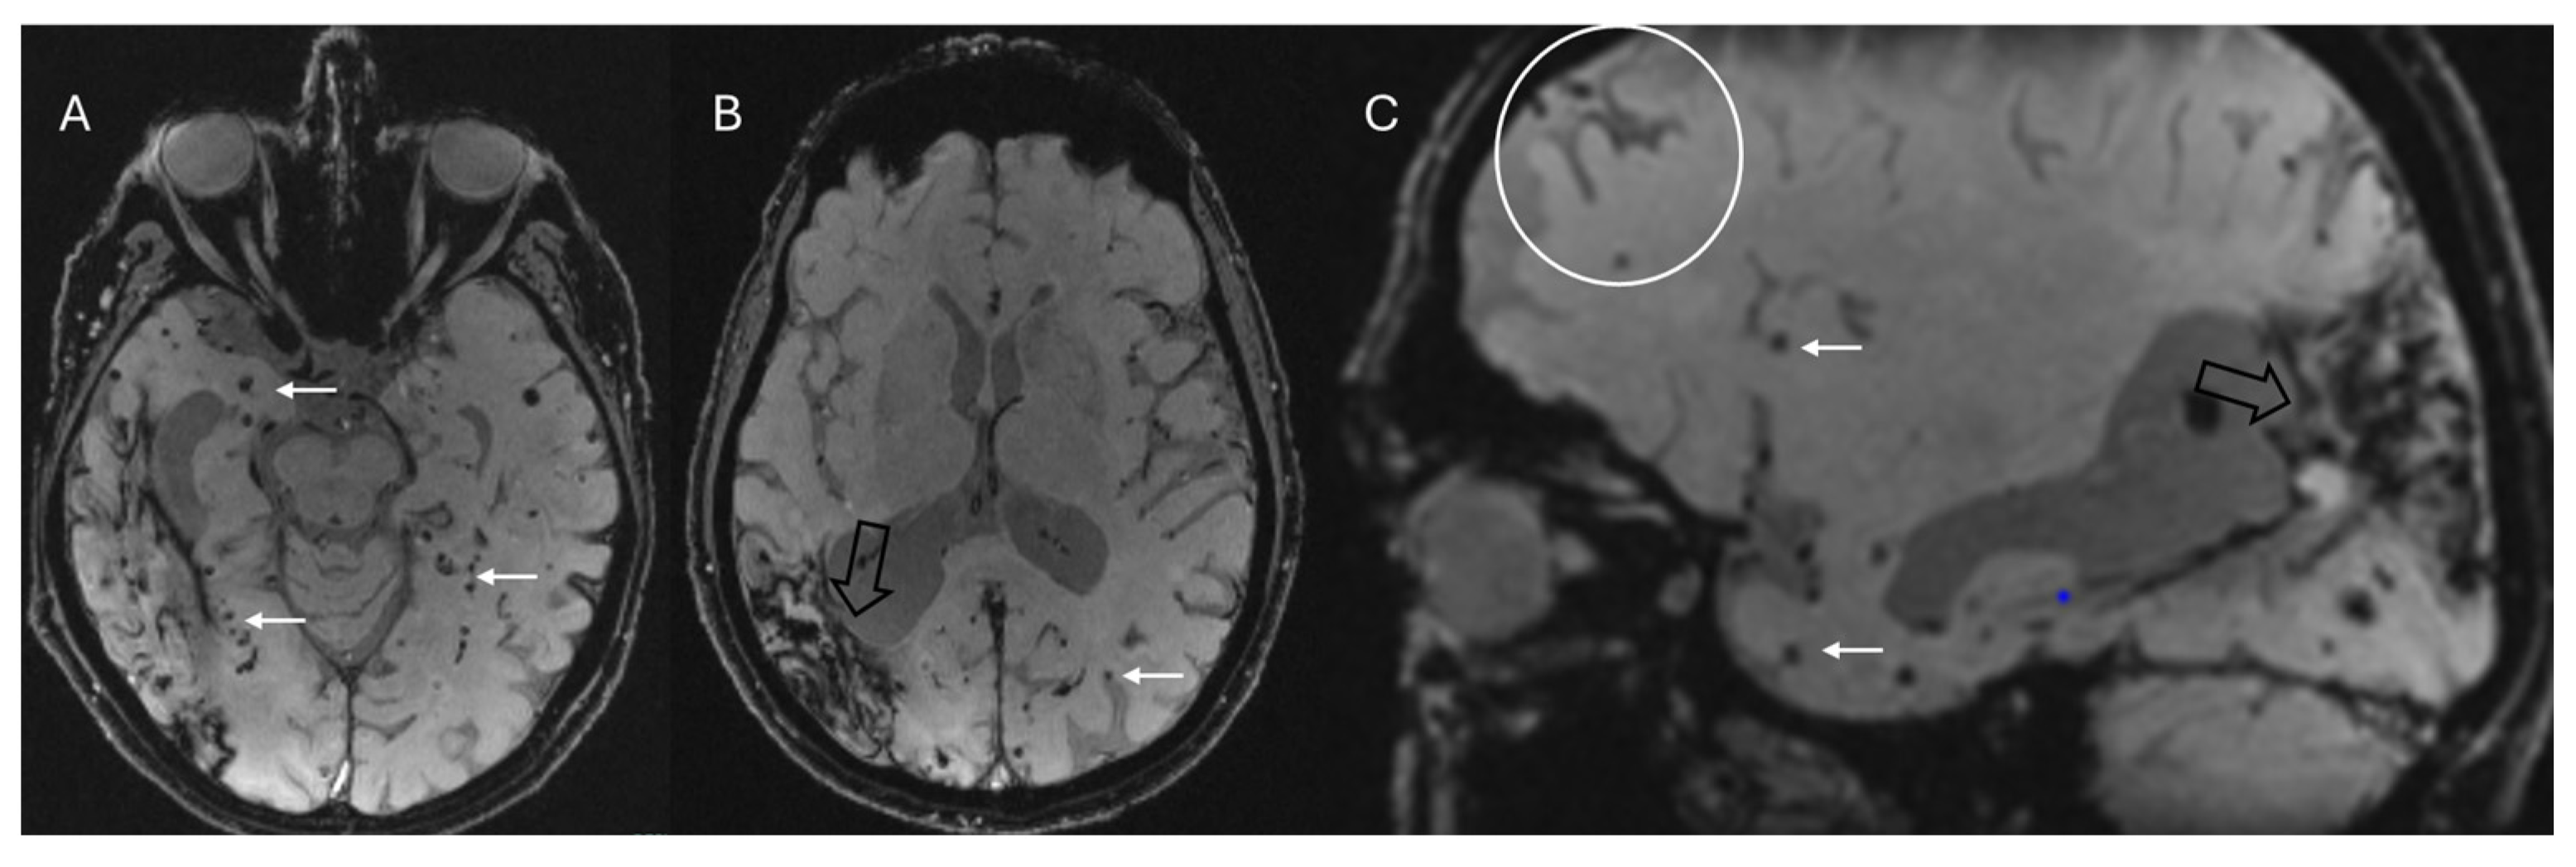

- Suh, C.H.; Kim, S.J.; Jung, S.C.; Choi, C.G.; Kim, H.S. The “Central Vein Sign” on T2*-weighted Images as a Diagnostic Tool in Multiple Sclerosis: A Systematic Review and Meta-analysis using Individual Patient Data. Sci. Rep. 2019, 9, 18188. [Google Scholar] [CrossRef]

- Maggi, P.; Sati, P.; Nair, G.; Cortese, I.C.M.; Jacobson, S.; Smith, B.R.; Nath, A.; Ohayon, J.; van Pesch, V.; Perrotta, G.; et al. Paramagnetic Rim Lesions are Specific to Multiple Sclerosis: An International Multicenter 3T MRI Study. Ann. Neurol. 2020, 88, 1034–1042. [Google Scholar] [CrossRef]

- La Rosa, F.; Wynen, M.; Al-Louzi, O.; Beck, E.S.; Huelnhagen, T.; Maggi, P.; Thiran, J.-P.; Kober, T.; Shinohara, R.T.; Sati, P.; et al. Cortical lesions, central vein sign, and paramagnetic rim lesions in multiple sclerosis: Emerging machine learning techniques and future avenues. NeuroImage Clin. 2022, 36, 103205. [Google Scholar] [CrossRef]

- Meaton, I.; Altokhis, A.; Allen, C.M.; A Clarke, M.; Sinnecker, T.; Meier, D.; Enzinger, C.; Calabrese, M.; De Stefano, N.; Pitiot, A.; et al. Paramagnetic rims are a promising diagnostic imaging biomarker in multiple sclerosis. Mult. Scler. J. 2022, 28, 2212–2220. [Google Scholar] [CrossRef]

- Chawla, S.; Kister, I.; Wuerfel, J.; Brisset, J.C.; Liu, S.; Sinnecker, T.; Dusek, P.; Haacke, E.M.; Paul, F.; Ge, Y. Iron and Non-Iron-Related Characteristics of Multiple Sclerosis and Neuromyelitis Optica Lesions at 7T MRI. Am. J. Neuroradiol. 2016, 37, 1223–1230. [Google Scholar] [CrossRef] [PubMed]